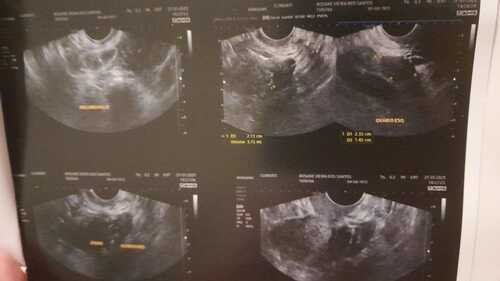

Há um mês descobri que tenho ENDOMETRIOSE profunda, que atingiu meu , se não for tratada a tempo. Recorri ao SUS, porém não me deram uma previsão de fazer a cirurgia e eu não posso esperar. A cirurgia particular custa R$10.000,00 ( Dez mil reais) vou precisar tirar o útero , trompas e um pedaço do intestino. Criei uma vaquinha para arrecadar o dinheiro e iniciar o tratamento. O pouco já ajuda muito!